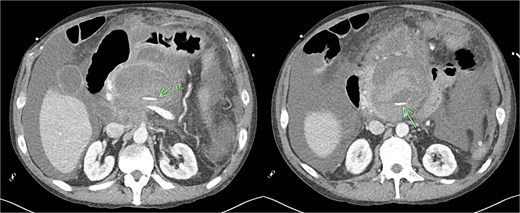

Despite the absence of abdominal symptoms, a computed tomography of the abdomen and pelvis (CTAP) was performed due to markedly elevated lipase levels. The CTAP (Figs 3–5) revealed evidence of acute pancreatitis (Fig. 5, arrow), with a complex peripancreatic fluid collection (Fig. 3, arrow). Additionally, a focal thrombus was observed within the portal venous confluence (Fig. 4, arrow). Further ultrasound of the gallbladder was negative for gallstones (Fig. 6), ruling out gallstone-induced pancreatitis.

CTAP coronal view; complex peripancreatic fluid collection (arrow) with extension behind the splenic vein to lie adjacent to the pancreatic neck and uncinate process.

CTAP coronal view; focal thrombus within the portal venous confluence (arrow).